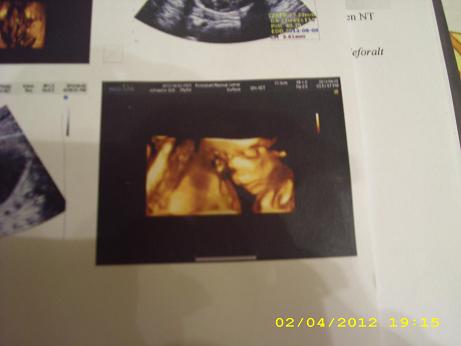

Újabb jobbnál jobb hírek!!! Csodás hír, hogy minden rendben van. Egyébként a képen a pofija alapján is nagyon csajszis Bogyóka! És csuda helyes!!!! És a pocakod!!!!! Nagyon szééééép!!!

De olyan szépek a meggymagjaitok!!!!